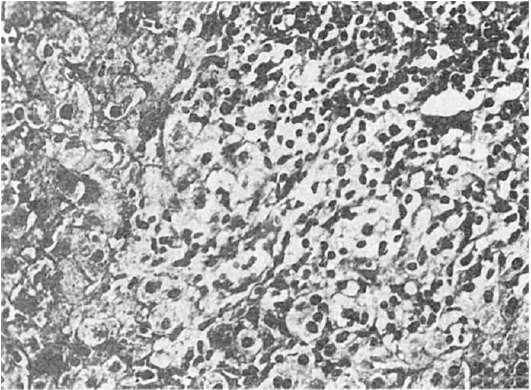

Преобладает гидропическая и баллонная дистрофия гепатоцитов, в различных отделах долек встречаются очаговые (пятнистые) и сливные некрозы гепатоцитов (рис. 214), тельца Каунсильмена в виде округлых эозинофильных гомогенных образований с пикнотичным ядром или без ядра (они представляют собой гепатоциты в состоянии коагуляционного некроза с резко уменьшенными в размерах органеллами - «мумифицированные гепатоциты»).

Портальная и внутридольковая строма диффузно инфильтрирована лимфоцитами и макрофагами с примесью плазматических клеток, эозинофильных и нейтрофильных лейкоцитов (см. рис. 214). Число звезд-

Рис.

214. Острый вирусный гепатит (биопсия печени). Баллонная дистрофия и некроз гепатоцитов. Лимфогистиоцитарный инфильтрат в портальном тракте и синусоидах

чатых ретикулоэндотелиоцитов значительно увеличено. Клетки инфильтрата выходят из портальной стромы в паренхиму дольки и разрушают гепатоциты пограничной пластинки, что ведет к появлению перипортальных ступенчатых некрозов. В различных отделах долек много переполненных желчью капилляров.